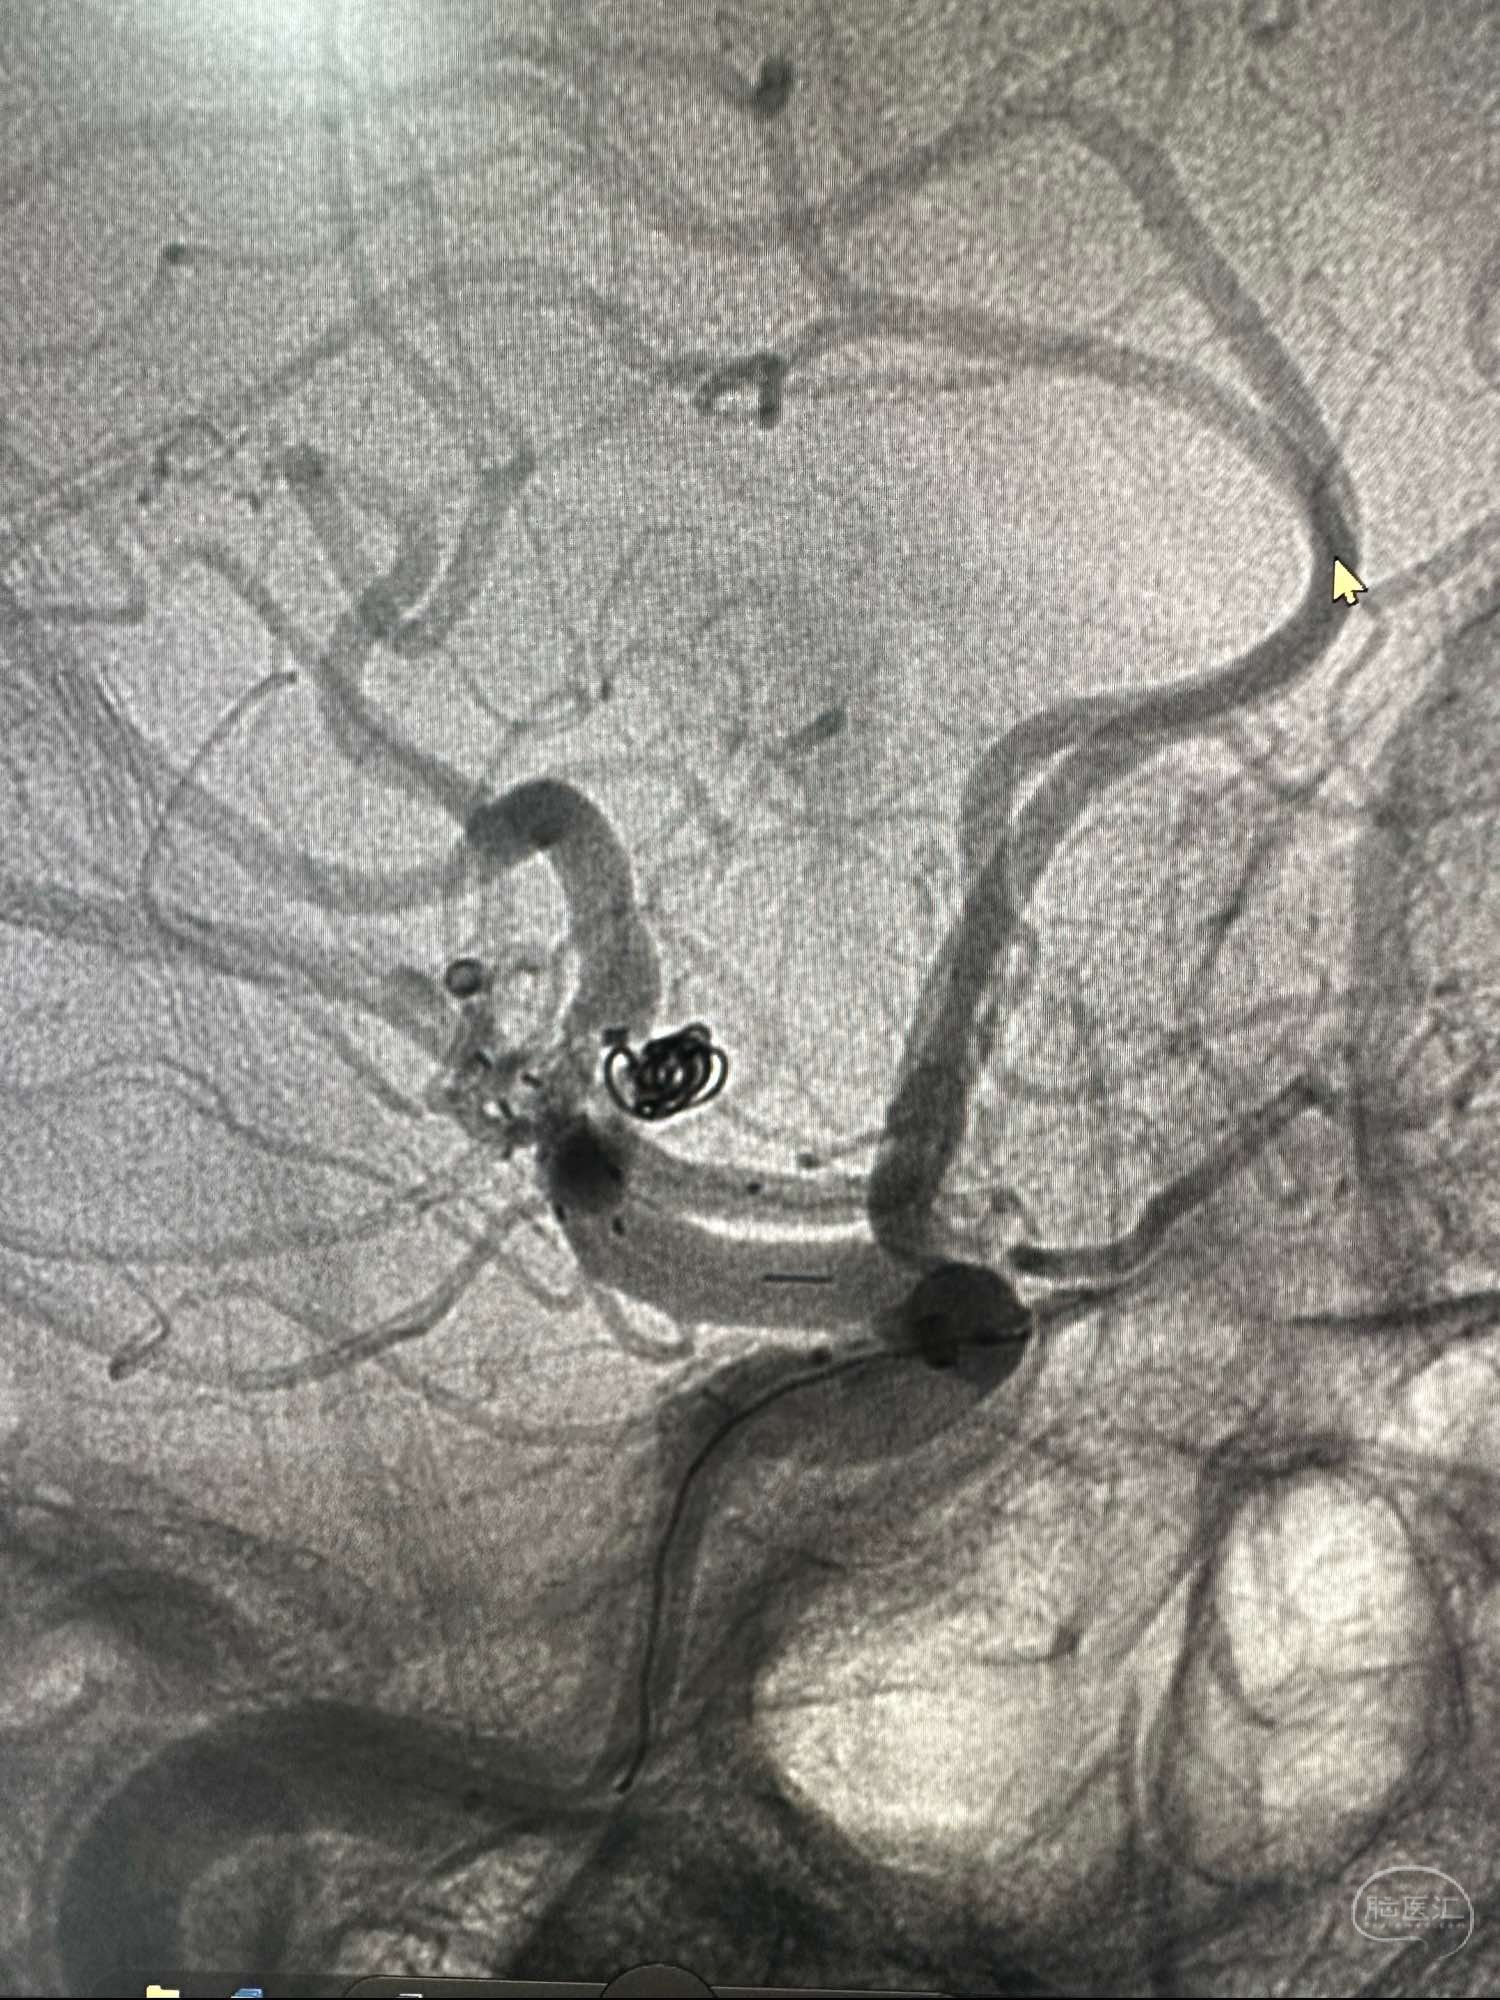

第一枚圈选择3*8的加奇的3D,出了几个襻后直接释放Atlas支架3*21

第一枚圈填塞后的形态,圈没有影响上干血流

第一枚圈的形态

后续再次填入2*4的加奇圈,另外一个角度造影见动脉瘤已经不显影

圈的形态